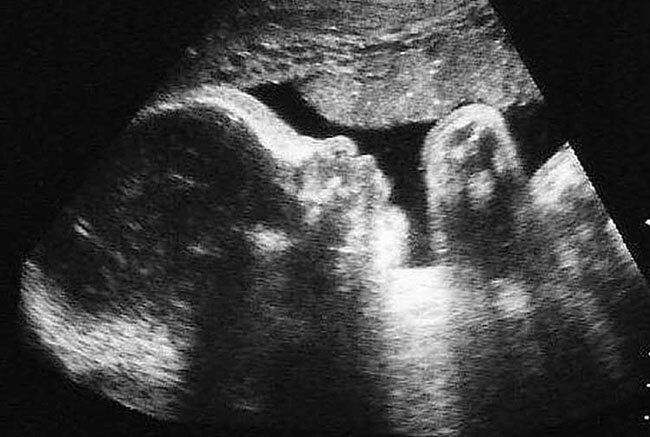

Для отслеживания протекания беременности, выявления отклонений в развитии плода и появления патологий современной медициной используется ультразвуковая диагностика беременности (УЗИ). УЗИ - одно из наиболее эффективных средств диагностики в современной медицине. Процедура безболезненна и безвредна для матери и ребенка и является добровольной. Ультразвуковая диагностика беременности по рекомендации врачей проводится на протяжении всего периода беременности и позволяет медикам в динамике наблюдать развитие плода и эффективно реагировать на возникающие отклонения. Первое ультразвуковое исследование рекомендуется проводить не раньше 10 – 14 недели, но бывают исключения. Для подтверждения факта беременности (когда наблюдается нарушение менструального цикла, но домашний тест не фиксирует факта беременности), при возникновении болей в области живота, кровотечений, при возможности многоплодной беременности, при беременности, возникшей в результате использования специальных репродуктивных техно

Для отслеживания протекания беременности, выявления отклонений в развитии плода и появления патологий современной медициной используется ультразвуковая диагностика беременности (УЗИ).

УЗИ - одно из наиболее эффективных средств диагностики в современной медицине. Процедура безболезненна и безвредна для матери и ребенка и является добровольной. Ультразвуковая диагностика беременности по рекомендации врачей проводится на протяжении всего периода беременности и позволяет медикам в динамике наблюдать развитие плода и эффективно реагировать на возникающие отклонения.